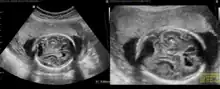

Fetal brain ultrasound scan at 24 weeks gestation: thalamic calcifications, hyperechogenic foci in right ventricular wall, asymmetric ventriculomegaly

Fetal brain ultrasound scan at 36 weeks gestation: microcephaly